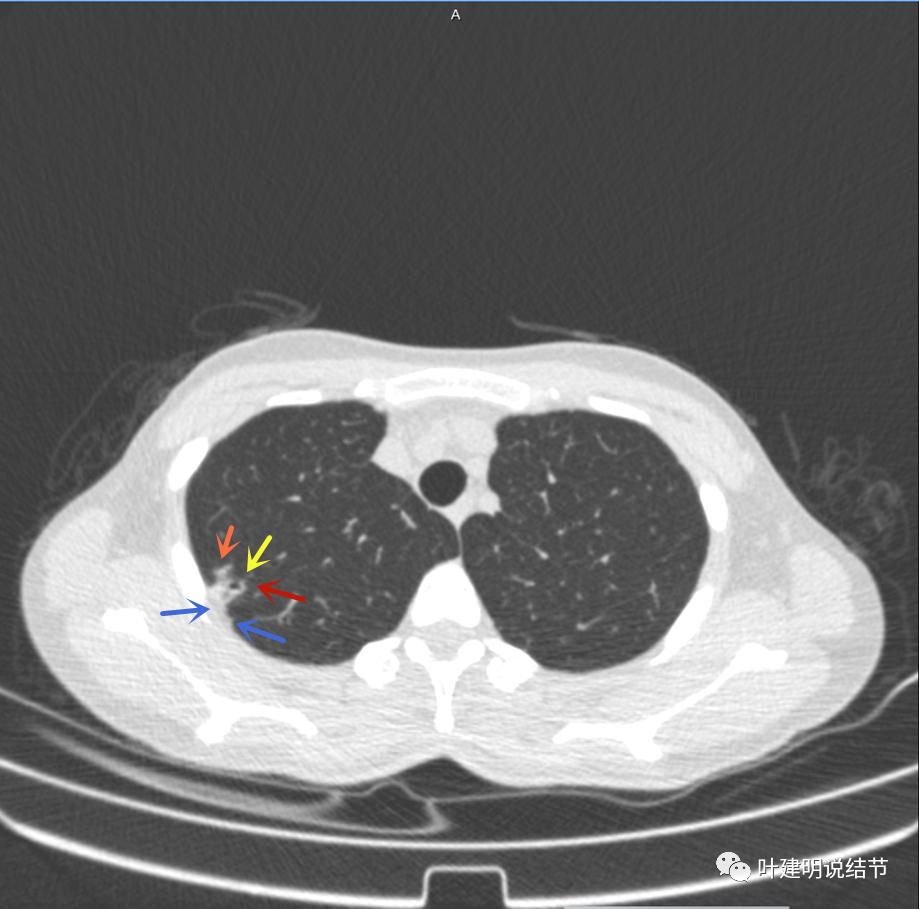

主病灶边界较清(红色箭头),实性部分密度过高(粉色箭头),病灶边缘向内凹,缺乏膨胀性(桔色箭头),病灶有空腔(黄色箭头)

邻近胸膜有增厚(蓝色箭头),主病灶的壁密度过高且整个壁密度都高(粉色箭头),旁边有磨玻璃影,散且模糊(砖色箭头)。内壁不均质(此不舒服)